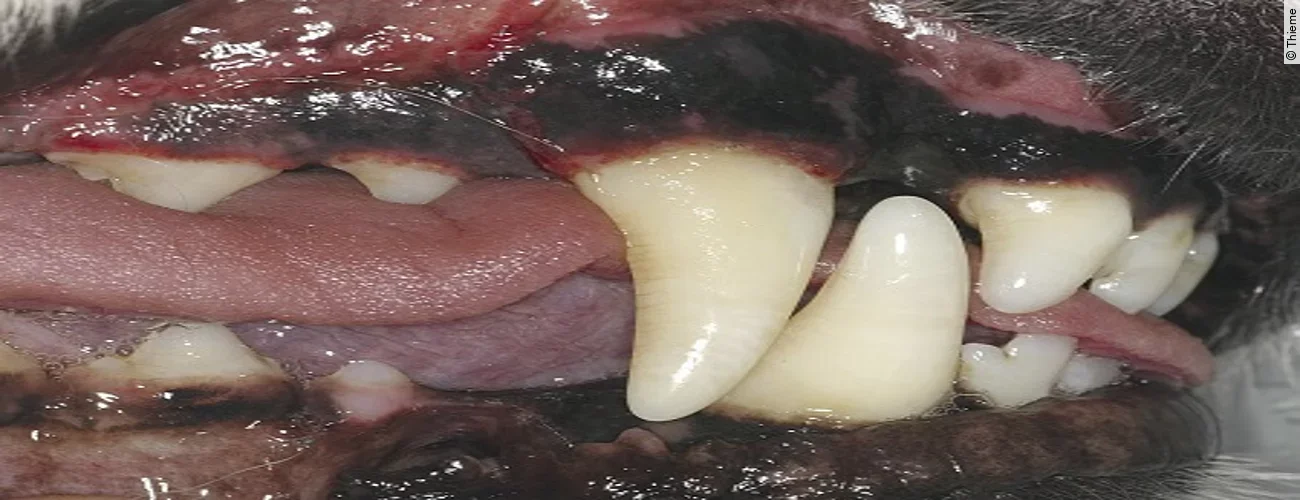

Finales Stadium der Luxation eines Zahnes ist dessen vollständiger Verlust, die Avulsion. Ist der herausgeschlagene Zahn intakt, so kann mittels Replantation eine Wiederherstellung der ursprünglichen Okklusion erreicht werden.

Replantation nach Avulsion Oberkieferfangzahn rechts

Der Originalartikel „Avulsion Oberkieferfangzahn rechts“ stammt aus dem Bild-Atlas der Zahnbehandlungen Hund und Katze; 2. aktualisierte Auflage; 2022.